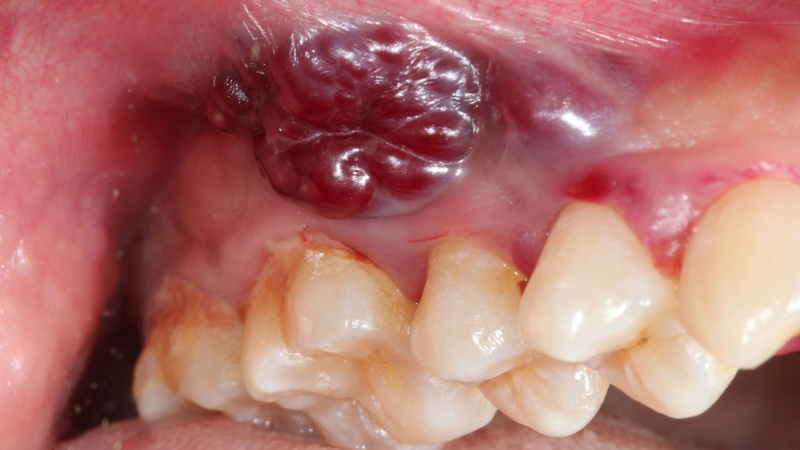

Ung thư miệng giai đoạn cuối là giai đoạn bệnh đã tiến triển nặng, khối u lan rộng và có thể di căn sang hạch cổ hoặc các cơ quan xa. Ở thời điểm này, mục tiêu điều trị không chỉ là kéo dài thời gian sống mà còn tập trung kiểm soát triệu chứng và nâng cao chất lượng cuộc sống cho người bệnh.

Ung thư miệng ở giai đoạn cuối (giai đoạn IV) là khi tế bào ung thư đã:

Ở giai đoạn này, khối u thường có kích thước lớn, gây đau nhiều, khó ăn uống và ảnh hưởng rõ rệt đến giao tiếp cũng như sinh hoạt hằng ngày. Người bệnh có thể gặp tình trạng suy kiệt thể lực, giảm sức đề kháng và dễ nhiễm trùng.

Ở giai đoạn cuối, triệu chứng thường rõ ràng và ảnh hưởng nặng nề đến chất lượng sống.

Tình trạng loét sâu, nhiễm trùng hoặc hoại tử mô có thể gây chảy máu và mùi hôi khó chịu, ảnh hưởng đến tâm lý người bệnh.

Hạch vùng cổ có thể to, cứng, dính chặt và ít di động - dấu hiệu cho thấy bệnh đã lan rộng.